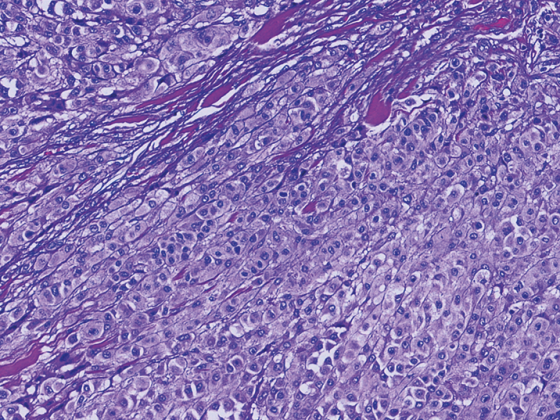

melanom_metastasierend_istock-1128205143

• Metastasiertes Melanom

Nach Stuhltransplantation besseres Ansprechen auf Immuntherapie